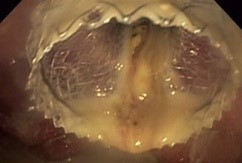

Hot AXIOS ™ Stent

Uso Clínico del Sistema de Entrega Mejorado de Cauterización Eléctrica y Stent de 20 mm Hot AXIOS™

Estudios de Casos Uso clínico del Sistema de Entrega Mejorado de Cauterización Eléctrica y Stent de 20 mm* para drenar Necrosis Pancreática Amurallada, por Douglas Adler, M.D., University of Utah, Facultad de Medicina, Huntsman Cancer Center, Salt Lake City, Utah.

El Dr. Adler utiliza el nuevo Stent Hot AXIOS de 20 mm para el tratamiento de gran colección de líquido pancreático (en el páncreas).